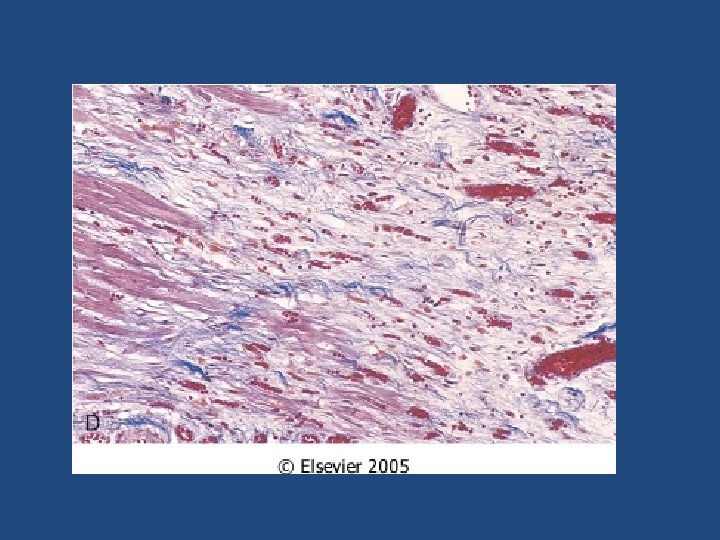

Ischemic Heart Disease MI types • Transmural – Full thickness (>50% of the wall) • Subendocardial – Inner 1/3 of myocardium – Two mechanisms: • Fixed atherosclerosis but with increased demand, vasospasm or hypotension OR • Evolving transmural with relieve of the obstruction (often multifocal)

Chronic ischemic heart disease • Progressive heart failure due to ischemic injury, either from: – prior infarction(s) (most common) – chronic low-grade ischemia